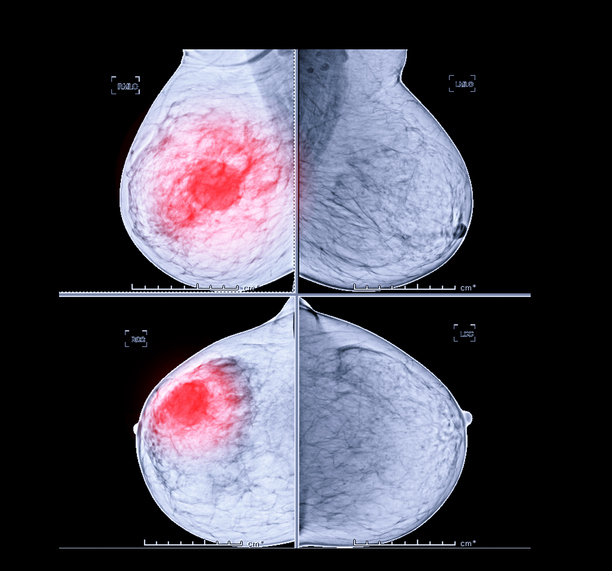

유방암은 유방에 생기는 악성 종양을 말합니다. 한국 여성에게 가장 많이 발생하는 암으로 여성암 발병률 1위였던 갑상선 암을 제치고 1위가 되었습니다. 전체 여성암 환자 중 1/5 이 유방암 환자에 해당한다고 하네요.

그나마 다른 암에 비해 예후가 좋은 편이긴 하지만 조기에 발견하고 치료하는 것도 중요합니다. 유방암 초기 증상에 대해 알아보도록 하겠습니다.

유방암 초기증상